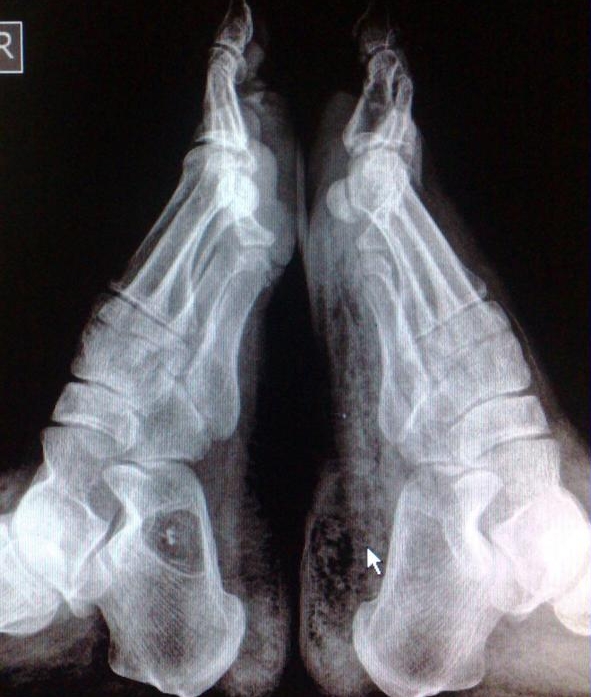

Наиболее распространенным методом диагностики данной патологии является рентгенография. Она позволяет выявить изменения в костных структурах, но для детей такая процедура не рекомендуется. Вместо этого им проводят ультразвуковое исследование области пятки. Хотя этот метод иногда может быть недостаточно информативным, в некоторых случаях он помогает выявить аномалии.

Наиболее точным способом диагностики считается магнитно-резонансная томография. Этот метод позволяет оценить состояние костей и изучить мягкие ткани. С его помощью можно легко обнаружить кисту. Исследование выполняется под разными углами, что помогает точно определить размеры образования, его структуру и особенности.